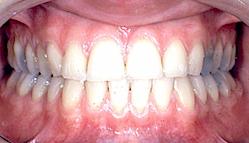

Il ne suffit pas d'observer les arcades en occlusion pour affirmer qu'il n'existe aucune pathologie comme cela a pu être déclaré par un expert judiciaire.